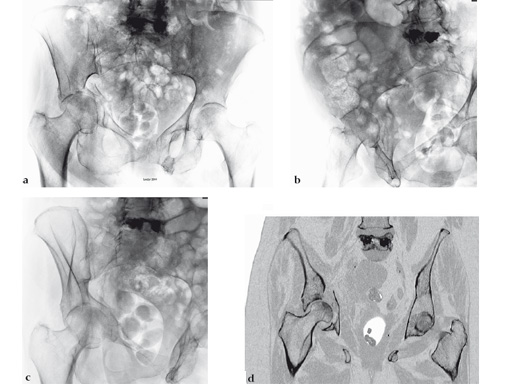

Case provided by Keith Mayo, Tacoma, USA: An elderly woman with steroid-dependent chronic obstructive pulmonary disease on home oxygen sustained an anterior column plus posterior hemitransverse acetabular fracture in a ground-level fall from her electric scooter.

Fig 1ad AP pelvis, Judet oblique, and coronal CT scan views of associated anterior column plus posterior hemitransverse acetabular fracture. This pattern is problematic for multiple reasons, including mild impaction of virtually the entire weight-bearing surface with additional separate impaction of the displaced anterior column, quadrilateral surface comminution, and severe osteoporosis.